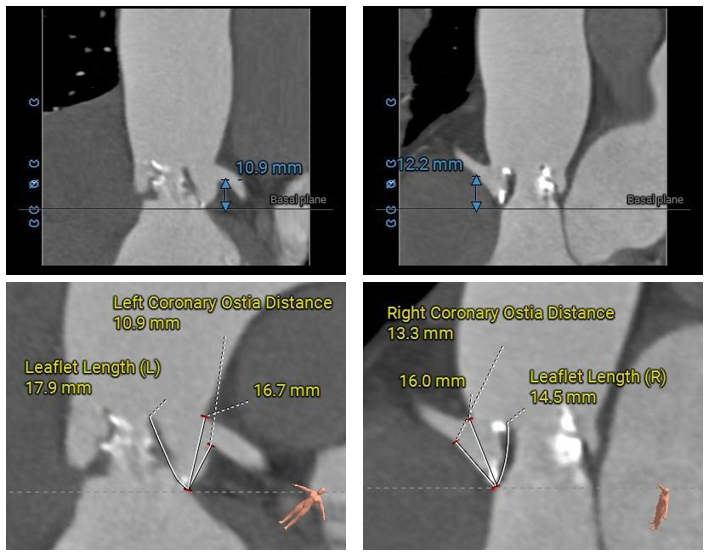

冠脉分析

左冠开口较低,双侧瓣叶冗长,预估双侧冠脉均存在一定遮挡风险。